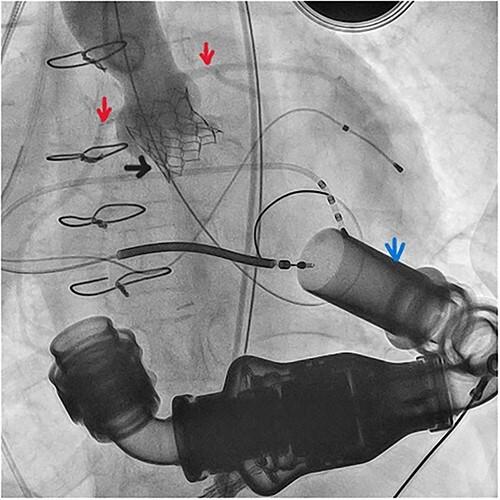

De novo aortic regurgitation (AR) presents a great challenge following left ventricular assist device (LVAD) implantation and requires valve replacement in some cases. Patients with LVAD are frequently those who underwent multiple previous sternotomies or suffer from multiple comorbidities. Thus, they are at high surgical risk for further sternotomy. Transcatheter aortic valve implantation (TAVI) previously approved for treatment of severe aortic stenosis is also used for this category of patients. Here, we report the case of a young female patient supported with heart mate II LVAD who presented with severe de novo AR. The patient was successfully treated with TAVI using Myval trancatheter heart valve (THV) in our center. To our knowledge, our patient is the first to be treated with such type of valve using TAVI procedure in LVAD supported patients.

植入左心室辅助装置(LVAD)后,新发主动脉瓣反流(AR)带来了巨大挑战,在某些情况下需要进行瓣膜置换。LVAD患者通常是那些之前接受过多次胸骨切开术或患有多种合并症的人。因此,他们接受进一步胸骨切开术的手术风险很高。先前被批准用于治疗严重主动脉瓣狭窄的经导管主动脉瓣植入术(TAVI)也用于这类患者。在此,我们报告一例接受HeartMate II LVAD支持的年轻女性患者,该患者出现严重新发AR。在我们中心,该患者使用Myval经导管心脏瓣膜(THV)通过TAVI成功治疗。据我们所知,我们的患者是首例在LVAD支持的患者中使用此类瓣膜通过TAVI手术进行治疗的。